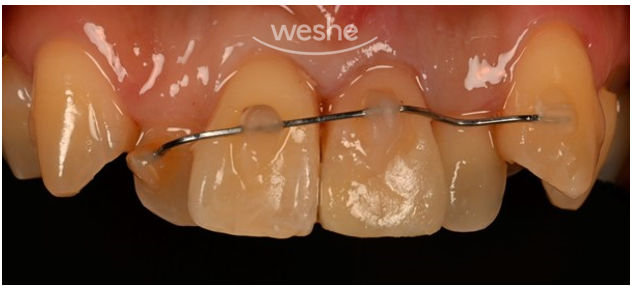

위 사진은 환자분의 입 안 모습입니다.

왼쪽 위 앞니 부위(사진상 오른쪽)가 깨져 있는 게 확인됩니다.

환자분 말씀으로는,

다치자마자 방문하신 치과의원에서

선생님께서 응급처치를 아주 잘해주셨다고 해요.

치아가 부러지며 잇몸 속으로 밀려 들어갔었는데,

그 치아를 다시 제 위치에 맞게 옮기고,

치아가 흔들려 철사로 고정까지 해주셨다고 합니다.

응급 대처가 정말 중요했던 순간이었는데,

먼저 진료해주신 선생님의 빠른 판단과 처치 덕분에

치아의 예후도 훨씬 좋아질 수 있었을 거라 생각됩니다.

환자분께서는 사회생활 중 말하거나 웃을 때

치아가 깨진 부위가 보일까봐 불편함을 느끼신다고 하셨습니다.

그래서 치료 전 단계에서 심미적인 불편을 줄일 수 있도록,

임시 보강 치료를 진행해드렸습니다.